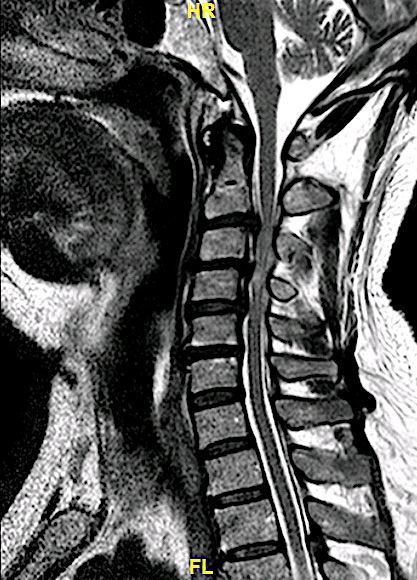

Paciente con clínica de mielopatía que presenta esta RM cervical con una estenosis de canal en segmentos tan inusuales.